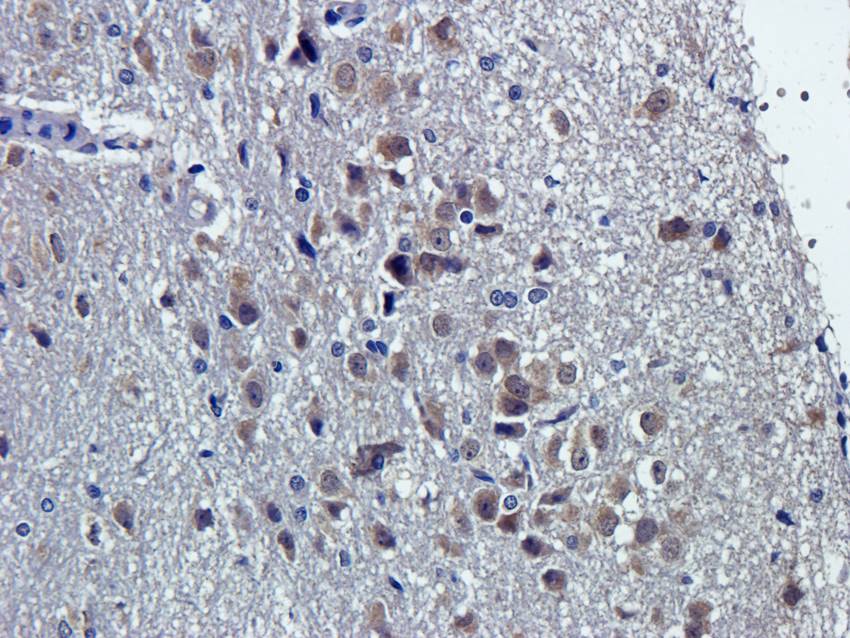

100 μg - FOXP3 antibody [orb34127]Featured

ELISA, ICC, IF, IHC-P, WB

Human, Mouse, Rat

Rabbit

Polyclonal

Unconjugated

100 μg - OPG antibody [orb247239]Featured